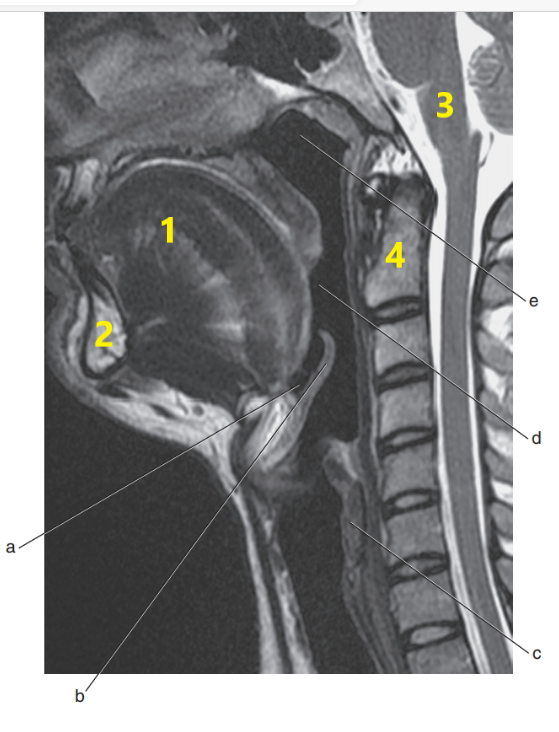

What is # 1 ?

Mandible

What is # 4 ?

C-1/C-2

Tongue

Epiglottis

Soft palate

What is # 1's ?

Cervical spine

What is letter e ?

What is # 3 ?

Brain stem